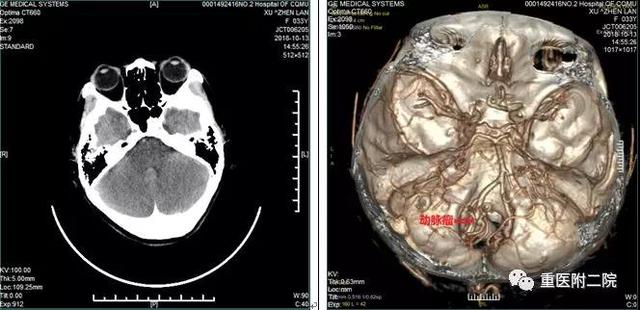

此次接受锁孔手术的患者为33岁女性患者,因“突发炸裂样头痛3天”在石柱县人民医院首诊,考虑颅内动脉瘤破裂,在住院期间再次发生破裂后,患者慕名来我院治疗。

患者在入院时神志清醒,肢体运动正常,颈抵抗阳性。头部CT显示自发性蛛网膜下腔出血,CTA确诊为颅内多发动脉瘤(左侧小脑后下动脉瘤,右侧颈内动脉床突段动脉瘤)。根据病情及影像学检查,左侧小脑后下动脉瘤是破裂的责任动脉瘤。